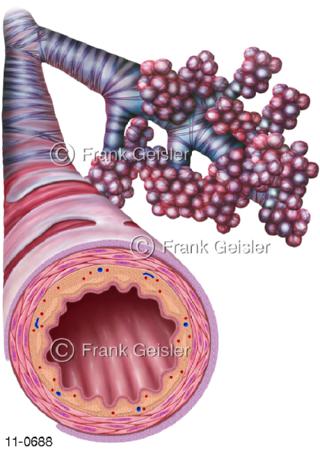

11-0688 Atemtrakt Atemwege, Bronchien mit Lungenbläschen